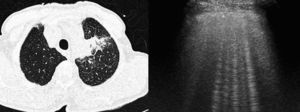

Enfermedades que cursan con afectación de los septos interlobulillaresHay múltiples procesos patológicos que cursan con afectación de los septos interlobulillares, cuya localización periférica en el pulmón los hace fácilmente valorables por ecografía, y que se han descrito como artefactos en cola de cometa12,65. Estos artefactos son visibles en condiciones normales66, pero en determinadas enfermedades que cursan con afectación de los septos interlobulillares se visualiza un aumento del número de artefactos en cola de cometa en la superficie pleural67 (fig. 6). Por el contrario, en pacientes con EPOC se ha descrito un número menor de estos artefactos.

Tomografía computarizada de tórax (izqda.): neoplasia pulmonar en el lóbulo superior izquierdo, con engrosamiento de septos interlobulillares, indicativo de linfangitis carcinomatosa. Ecografía torácica (dcha.): múltiples artefactos de cola de cometa que traducen el engrosamiento de los septos interlobulillares.

En las unidades de cuidados intensivos este hallazgo es útil para distinguir a los pacientes con EPOC de aquéllos con insuficiencia cardíaca5,68–70, con una sensibilidad del 100% y una especificidad del 92% para la detección de edema pulmonar68. Incluso se ha descrito la relación existente entre el número de artefactos en cola de cometa y el grado de insuficiencia cardíaca71,72, lo que permite el seguimiento de estos pacientes73.